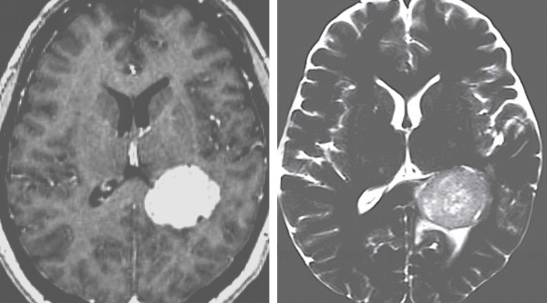

图6. 高级别胶质瘤具有不规则的边界和结节,呈不均匀的强化表现。在T2相上表现为高信号。位于透明隔的肿瘤与神经细胞瘤相似。

图8. 脑膜瘤表现为显著的均一强化,边界清楚,伴有脑膜尾征。在T2相上典型地表现为高信号。侧脑室脑膜瘤最常见于房部。